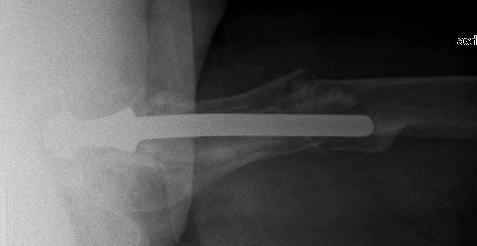

Reminded me of a case I did a couple years ago - 30 year old woman with juvenile rheumatoid arthritis and a nonunion below her stem. Fixed with retrograde nail which docked with the stem and a lateral locking plate. Image attached. One of the companies should come up with a stem design and nail system that anticipates this need.